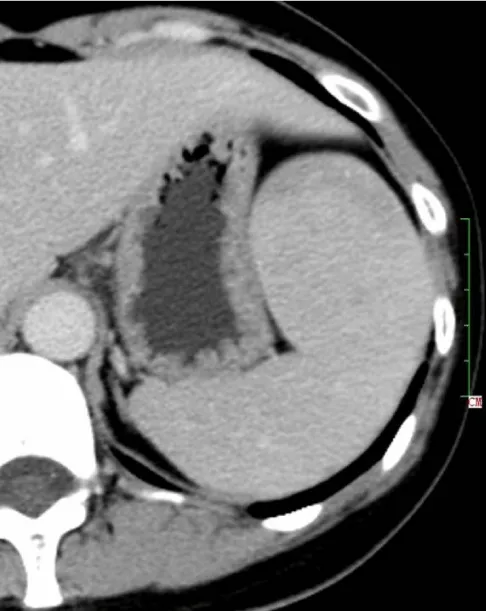

Solitary well-circumscribed masses were detected in all the five patients by ultrasound. One mass was of hypoecho, while the remaining masses were of hyperecho with posterior enhancement (Figure 1A). The maximum diameter ranged from 3.0 cm to 9.0 cm. At CT scanning, two masses appeared as hypodense (Figure 1B) and one was isodense (Figure 2A) to the normal spleenic parenchyma. In the two patients who received MR imaging, masses were isointensity at T1 weighted images (Figure 3A) and hypointensity with scattered sign void spots at T2 weighted images (Figure 3B). After intravenous injection of the contrast materials, all the five masses presented circle enhancement at arterial phase (Figure 3C and Figure 4A), while peripheral enhanced node was noted in one mass (Figure 2B). The circle enhancement persisted and radical line enhancement were observed at portal vein phase in 3 cases (Figure 1C) and progressive filling in was seen in two cases (Figure 2C). At delay phase of MR imaging, one lesion showed obvious enhancement with stellate low signal scar in the center comparing with surrounding splenic parenchyma (Figure 3D), while the other demonstrated central and circle enhancement to form a spoke-like appearance (Figure 4B). At delay enhanced CT scanning, two masses were isoattenuation to the surrounding splenic parenchyma (Figure 2D) and one lesion kept as hypoattenuation but with radial enhanced lines and enhanced circle to form a spoke-like appearance.

At pathological examination, all the masses were well demarcated on gross cut surface. A central stellate scar with peripheral interspersed dark brown nodules and the whitish intervening fibrous bands was noted to form spoke-like appearance (Figure 3E), which was well correlated with CT and MR imaging findings at enhancement. Microscopically, these angiomatoid nodules were surrounded by dense concentric collagen fibrous stroma and dispersed stromal cells with oval-to-spindle nuclei and scanty cytoplasm (Figure 3F). The abunden fibrous stroma may result in hypointensity at T2 weighted MR images. Hemosiderin was noted in the angiomatoid nodules (Figure 3G), which might contributed to signal void at T2 weighted MR images.

It usually affects middle-aged adults [6] and it is commonly found incidentally on radiographic imaging, or during operation for an unrelated condition. In present series, the patients are middle-aged adults without any related symptoms and the lesions were detected incidentally at routine ultrasound of health examinations. On ultrasound, manifestations of SANTs are vary widely from heterogeneous echo-texture with hyperechogenic, hypoechogenic, or isoechogenic appearing lesions, which are unspecific [7,8]. CT and MRI can show some characteristic features of SANTs, which include a solitary well demarcated mass with early peripheral enhancemant with radiating lines and progressive enhancement at the delay phase, and hypointens at T2 weighted MR images [2,3,5,9-13]. These features reflect the underlying pathological changes of scattered angiomatoid nodules separated and surrounded by sclerotic fibrotic stroma [10]. In present series, we also observed these characteristic features with well correlation to pathological findings. Circle and spoke-like enhancement can be contributed to fibrotic stroma surrounding and separating the angiomatoid nodules. The sclerotic fibrotic stroma may also result in isodense on CT, isointensity on T1 weighted images and hypointensity on T2 weighted images of MR imaging. The signal void spots at T2 weighted MR images have not been described at other literatures and may be contributed to hemosiderin deposition due to magnetic susceptibilty artifact.